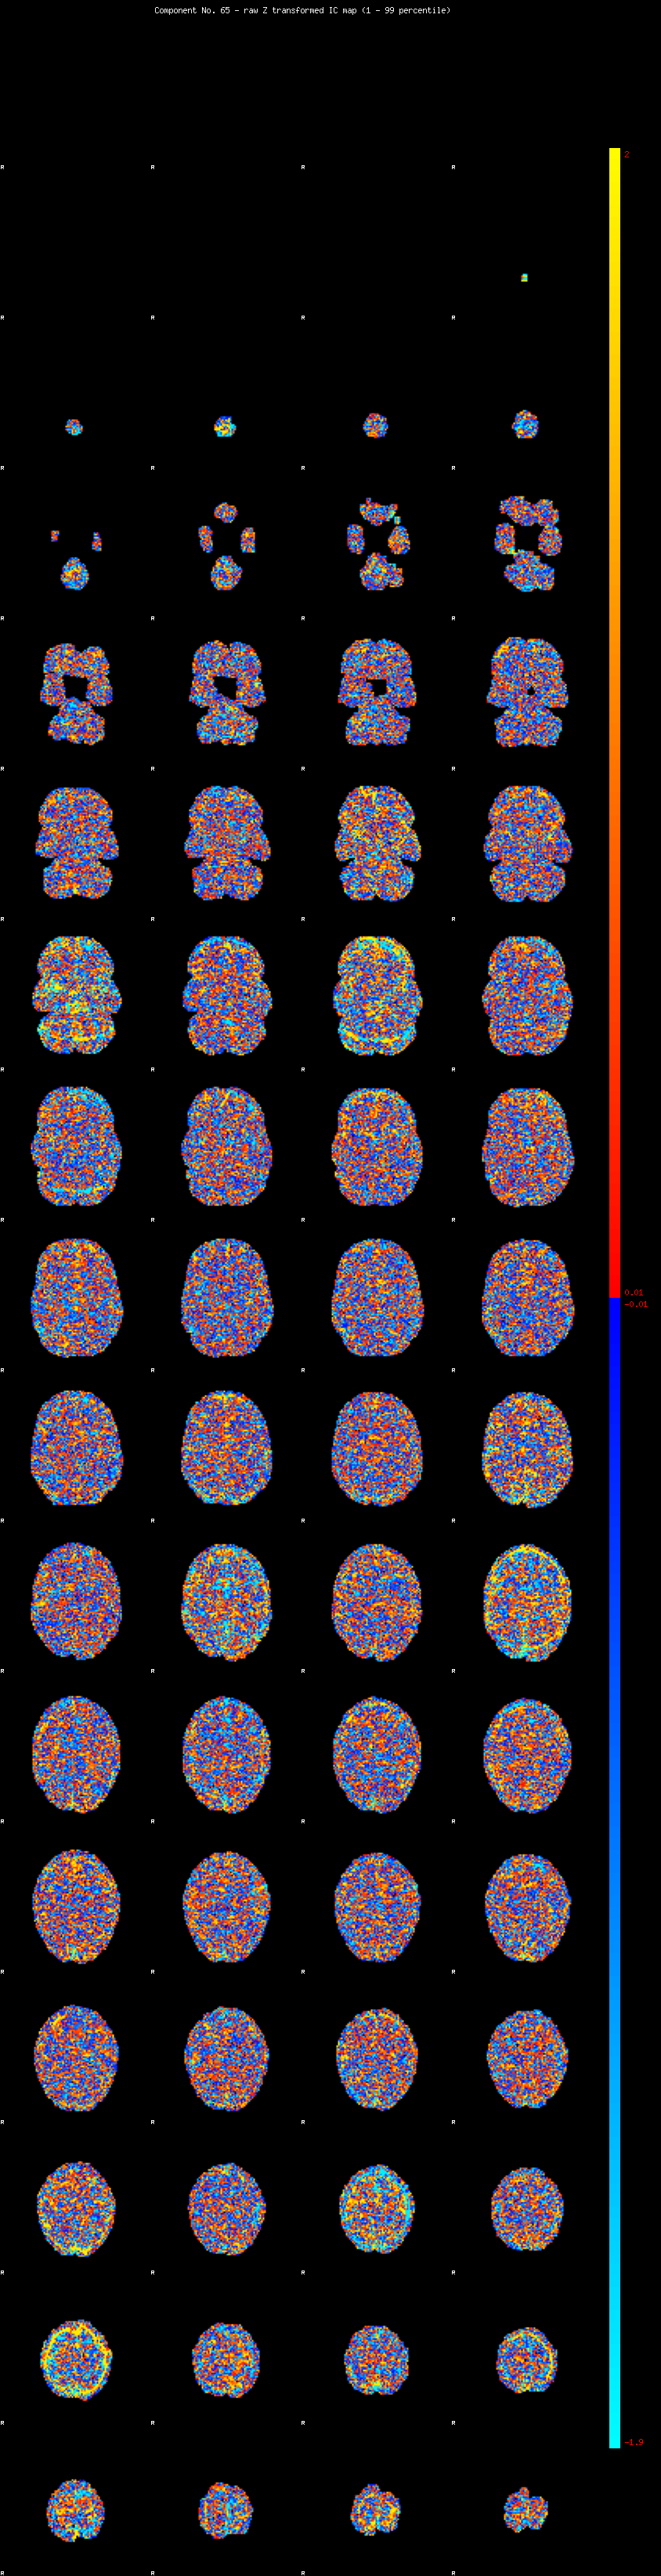

IC_65 Mixture Model fit

Means : 0.000000 2.269872 -2.286818

Vars : 1.000000 1.370954 1.175398

Prop. : 0.941010 0.035146 0.023844